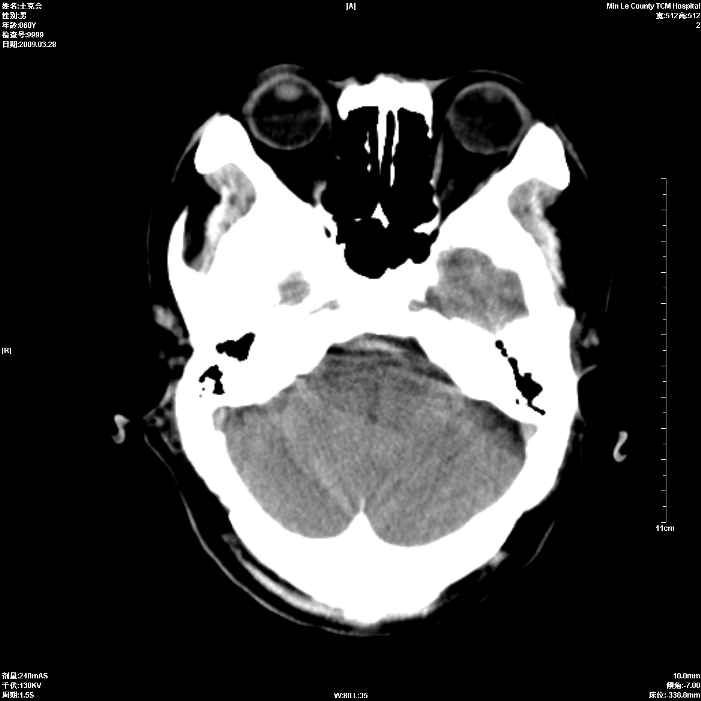

标题: CT19074:患者男60岁头晕头痛一月, [打印本页]

标题: CT19074:患者男60岁头晕头痛一月,

考虑额叶脑转移瘤,建议ct增强

考虑双侧额叶脑转移瘤;建议行进一步检查。

双侧额叶转移瘤

占位征像加水肿带,建议ct增强。

双侧额叶均有低密度影,考虑:1、嗅沟脑膜瘤。2、转移瘤。 建议增强扫描进一步检查。